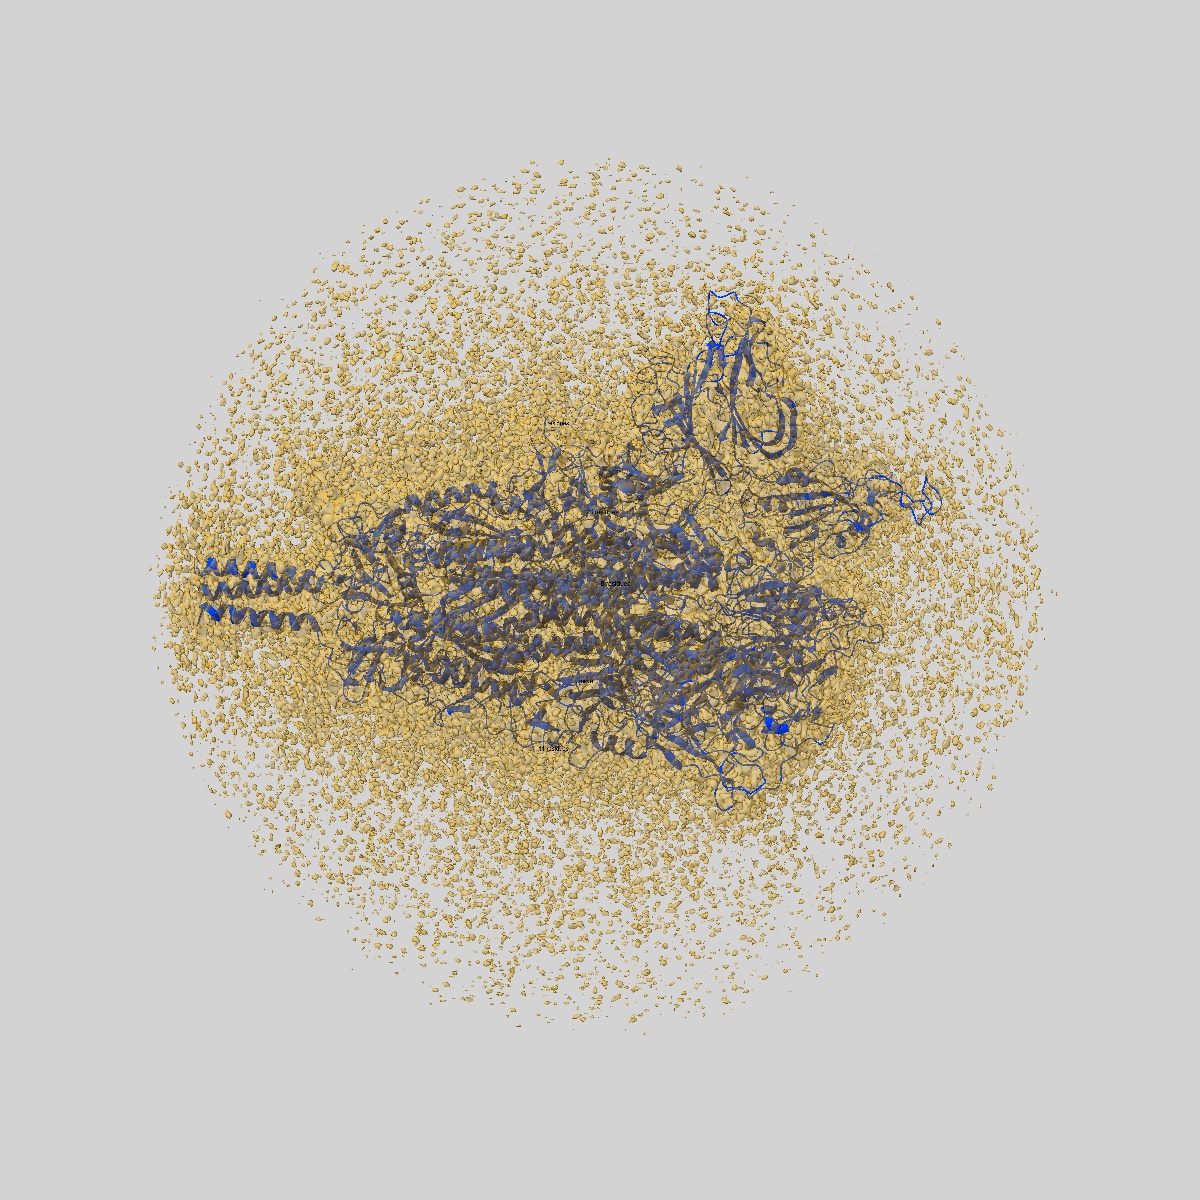

JN.1 SARS-COV-2 Spike 1-up conformation

Sample: S protein trimer

Fitted models: 9d8i

SARS-CoV-2 JN.1 and KP.2 spike characteristics and neutralization of JN.1-derived sublineages and T cell responses from mice immunized with monovalent JN.1- and KP.2-adapted BNT162b2 COVID-19 vaccines